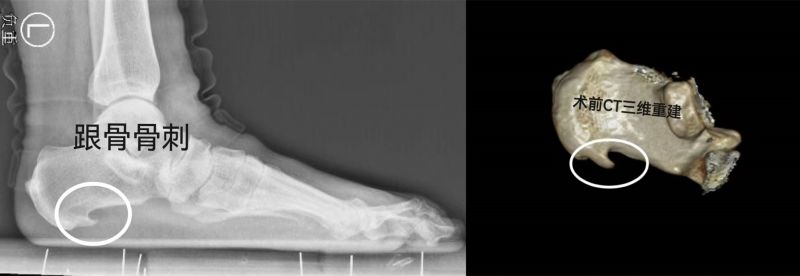

55岁的烟台市民刘女士因“左侧足跟反复疼痛2年余,加重2个月”前来就诊。此前刘阿姨曾尝试多种保守治疗,效果均不理想。经多方了解和打听后慕名来到烟台山医院足踝外科门诊就诊,曲文庆主任医师接诊后,通过查体发现患者左侧足底后跟部压痛明显,经筛查排除了痛风、类风湿关节炎、骨折、骨髓炎等相关疾病,X线片可见左侧跟骨骨质增生、伴骨刺形成,综上诊断为“左足跟骨骨赘伴足底跖筋膜炎”。经过认真充分的术前讨论,科室制定了微创手术方案——关节镜下跟骨骨刺切除+足底跖筋膜松解术。当日的手术由刘彤主治医师历时半小时顺利完成,患者术后恢复良好。

曲文庆主任介绍说,跟骨骨刺是中老年人的常见病与多发病。据报道,在所有因足部疾患而就诊的患者中,有15%为跟痛症,而其中73%由跟骨骨刺引起。跟骨骨刺的症状表现与骨刺的大小、发病时间长短、有无炎症等有关。主要表现为足跟压痛,脚底疼痛,早晨重,起床下地第一步痛不可忍,严重时患者会突然摔倒,活动开后症状减轻,走动增多后疼痛又加重,病情反反复复,迁延不愈。大部分患者可采用穿软底鞋、使用跟骨骨刺垫,进行牵伸训练,应用非甾体类抗炎镇痛药,接受冲击波治疗等方法,疼痛大都能得到缓解。对于上述办法仍无很好疗效的患者而言,接受微创手术将是不错的选择。